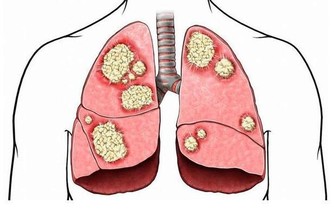

肝臟是人體主要以代謝功能為主的一個器官,也是人體最大的器官。每年全球新患肝癌人數為74.8萬人,有50%發生在中國,除此以外,預計,肝炎、脂肪肝、肝癌、酒精肝等慢性肝臟疾病,我國2020年總數將達4.47億人,對人的傷害不容小覷,早發現早治療極為重要。